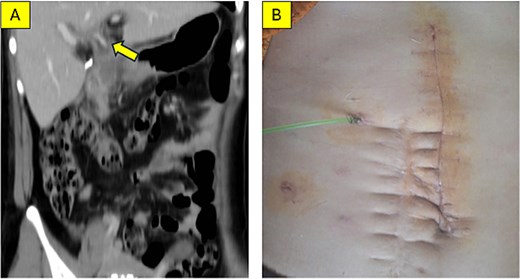

Examination of the opened specimen revealed a dilated cyst containing stones, food debris, and a papillary lesion on the cyst wall (Fig. 3A and B). Frozen section analysis confirmed adenocarcinoma arising from the cyst, with negative resection margins. Reconstruction involved extended lymphadenectomy, primary closure of the duodenal defect, and Roux-en-Y hepaticojejunostomy. A transanastomotic stent was placed. The postoperative course was uneventful; the patient was discharged on Day 7. Final pathology confirmed moderately differentiated adenocarcinoma with negative lymph nodes (0/5) (Fig. 4A and B).

Postoperative outcomes. (A) Coronal MSCT scan at 4 weeks post-surgery; the arrow indicates the transanastomotic stent (catheter) placed via the jejunal limb into the common hepatic duct. (B) Clinical photograph showing the healed incision and the external biliary drain.